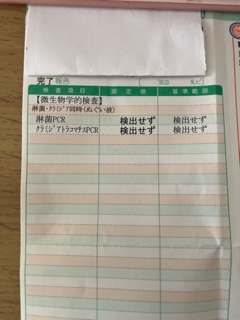

報告。おはようございます 先週から喉と胃腸の調子が悪くお休みしてました

先週から喉と胃腸の調子が悪くお休みしてました 今もまだアイスは禁止期間

今もまだアイスは禁止期間 お休みの間にしっかり冬支度と病院に

お休みの間にしっかり冬支度と病院に 婦人科の性病検査はするけど咽頭ってしたことなくて、喉の調子も悪かったのでついでに検査しました。ドキドキの結果は陰性

婦人科の性病検査はするけど咽頭ってしたことなくて、喉の調子も悪かったのでついでに検査しました。ドキドキの結果は陰性 検査するためのうがい液はしょっぱかった

検査するためのうがい液はしょっぱかった 婦人科の結果は本日朝イチで聞いてきました

婦人科の結果は本日朝イチで聞いてきました こちらも大丈夫でした